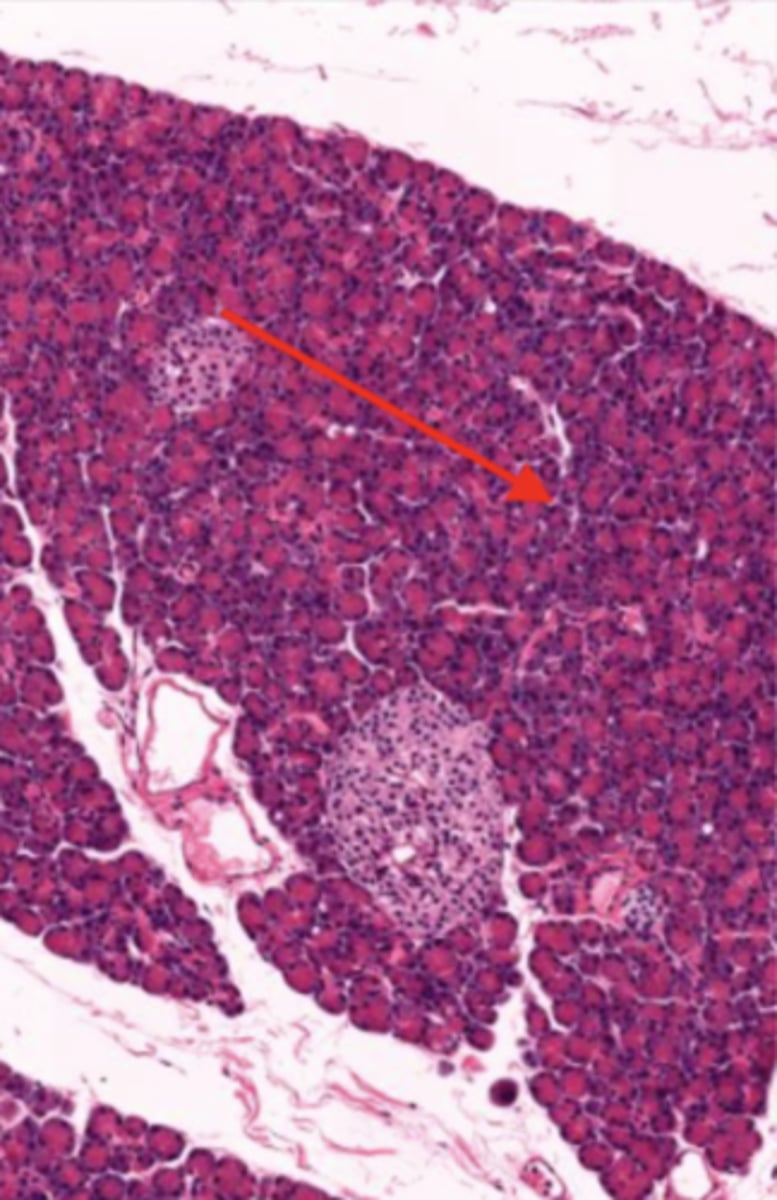

pancreas (histology)

Acinar cells (pancreas)